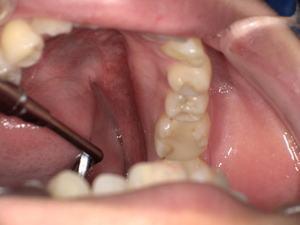

70代女性に対し、唾石摘出術を実施しました。

手術の流れ:

- 局所麻酔

- 口腔底粘膜を慎重に切開

- 唾石を確認・摘出

- 洗浄・縫合

- 術後腫れ・嚥下痛の管理

CTで石の位置や大きさを確認することで、最小侵襲で安全に摘出可能です。